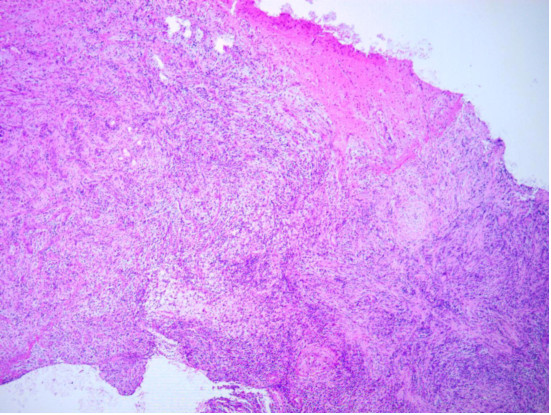

术后常规病理提示:(左侧顶叶)明显的炎症性改变,伴大量的小淋巴细胞和中性粒细胞及纤维化,小血管周围淋巴细胞套,炎症性病变。结合免疫组化s-100阳性,CD1a阴性,倾向Rosai-Dorfman病,已经排除胶质瘤、脑膜瘤、炎性肌纤维母细胞瘤、Langerhans细胞增生症(图3)。免疫组化结果:S-100 散在+,CD1a -,Ki-67 10%+,P53 -,CD68 +,SSTR2 局灶+,ALK-noneLung -,EMA 浆细胞+。

图3. 术后常规病理显示明显的炎症性改变,伴大量的小淋巴细胞和中性粒细胞及纤维化,小血管周围淋巴细胞套,提示Rosai-Dorfman病。